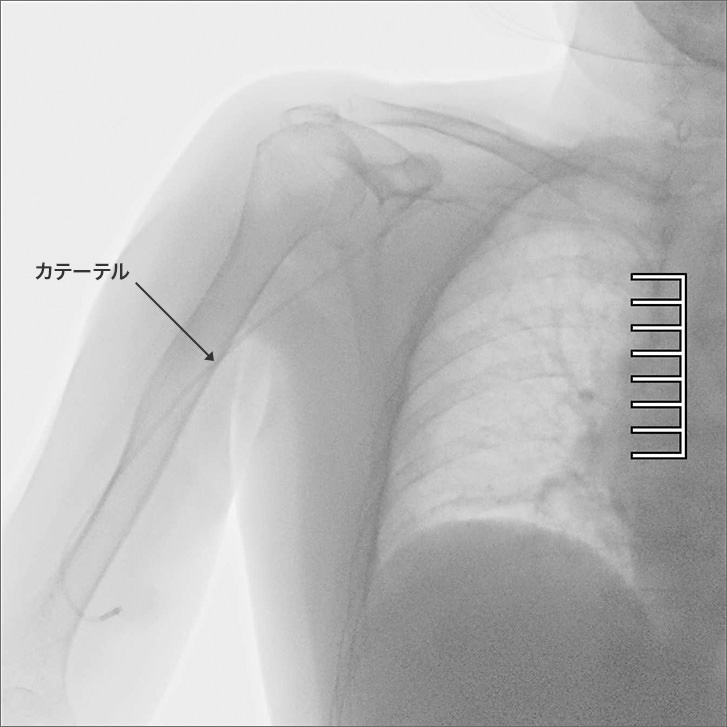

医師からも、高画質を実感しているという評価をもらっています。例えばCVカテーテル※を胸の血管に挿入する時、カテーテルが背骨の近くを通ります。空気が多く含まれる胸(肺)と骨では透視に必要な線量が違うので画質を合わせるのが難しいのですが、この装置では胸(肺)に合わせた低い線量でも、画像処理で画質が補われてコントラストの高い画像をリアルタイムでしっかり見ることができています。

- ※central venous catheter:中心静脈カテーテル(経口・経腸栄養が困難な場合に用いる栄養補給のためのカテーテル)